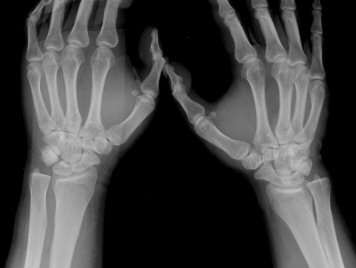

¼ºº° / ³ªÀÌ

³²ÀÚ/32¼¼

ÁÖÁõ»ó

¿ìÃø ¼Õ¸ñÀÇ ÅëÁõ

±³Åë »ç°í ÈÄ Å¸º´¿ø¿¡¼­ ¿¢½º·¹ÀÌ Âû¿µÇÏ°í ¿°Á Áø´ÜÇÏ¿¡ Àü¿øµÊ. 3ÁÖ ÈÄ ÅëÁõÀÌ °è¼ÓµÇ¾î ÃÊÁø º´¿ø¿¡¼­ Áֻ縦 ¸Â¾ÒÀ¸³ª Áõ»ó È£Àü ¾ø¾î ´Ù½Ã ³»¿ø

¼Õ¸ñÀÇ °üÀý °¡µ¿ ¹üÀ§°¡ °æ¹ÌÇÏ°Ô Á¦Çѵǰí ÁÖ»ó°ñ ºÎÀ§ ¾ÐÅëÀ» º¸ÀÓ

ÃÊÀ½ÆÄ °Ë»ç

¼Õ¸ñÀÇ Á¾´Ü

ÁÖ»ó°ñ ¼±»ó°ñÀýÀº ´Ü¼ø¹æ»ç¼± ÃÔ¿µ ½Ã È®ÀεÇÁö ¾ÊÀº °æ¿ì°¡ ¸¹Àºµ¥ ÀÌ ¶§ ÃÊÀ½ÆÄ

°Ë»ç°¡ ÁÖ»ó°ñ °ñÀý Áø´Ü¿¡ ¸Å¿ì À¯¿ëÇÏ´Ù. ±×·¯¹Ç·Î ¼Õ¸ñ ´ÙÄ£ ÈÄ Áö¼ÓÀûÀÎ ÅëÁõÀ»

È£¼ÒÇϰí ÁÖ»ó°ñ ºÎÀ§ ¾ÐÅëÀ» º¸ÀÌ´Â °æ¿ì ÃÊÀ½ÆÄ°Ë»ç¸¦ ½ÃÇàÇÏ¿© ÁÖ»ó°ñ °ñÀý ¿©ºÎ¸¦

È®ÀÎÇØ¾ß ÇÑ´Ù.

ÃÊÀ½ÆÄ°Ë»ç¸¦ ½ÃÇàÇÒ ¼ö ¾ø´Â °æ¿ì´Â ÄÄÇ»ÅÍ ÃÔ¿µ°Ë»ç¸¦ ÁÖ»ó°ñ °ñÀýÀ» È®ÁøÇÒ ¼ö ÀÖ´Ù.